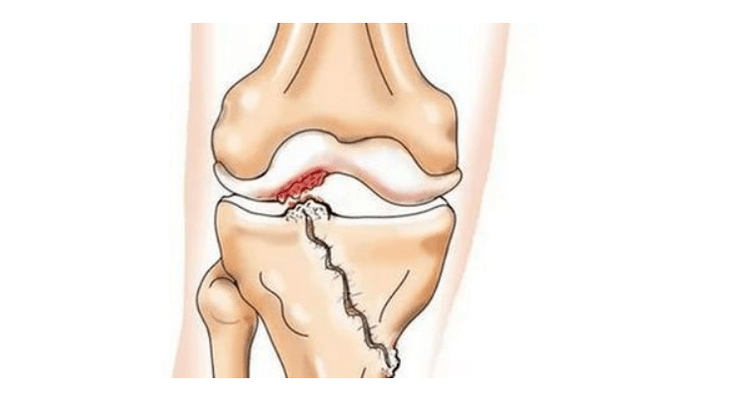

- lesioni (fratture, rotture del legamento meniscale e crociato anteriore). Sfortunatamente, in qualsiasi persona, indipendentemente dall’età, queste lesioni portano a uno stress eccessivo sulla cartilagine. Una frattura di qualsiasi parte delle ossa ricoperta di cartilagine è accompagnata dalla formazione di un'irregolarità - un "gradino". In quest'area, durante lo spostamento, si verifica l'abrasione e si forma l'artrosi;

Con l'artrosi (osteoartrosi), oltre alla progressiva distruzione della cartilagine, alla perdita della sua elasticità e delle proprietà ammortizzanti, le ossa vengono gradualmente coinvolte nel processo. Sotto carico compaiono bordi taglienti (esostosi), che vengono erroneamente considerati "depositi di sale" - nell'artrosi classica non si verifica alcun deposito di sale. Man mano che l’artrosi progredisce, continua a “mangiare” la cartilagine. Quindi l'osso si deforma, lì si formano delle cisti, tutte le strutture dell'articolazione vengono colpite e la gamba si piega.